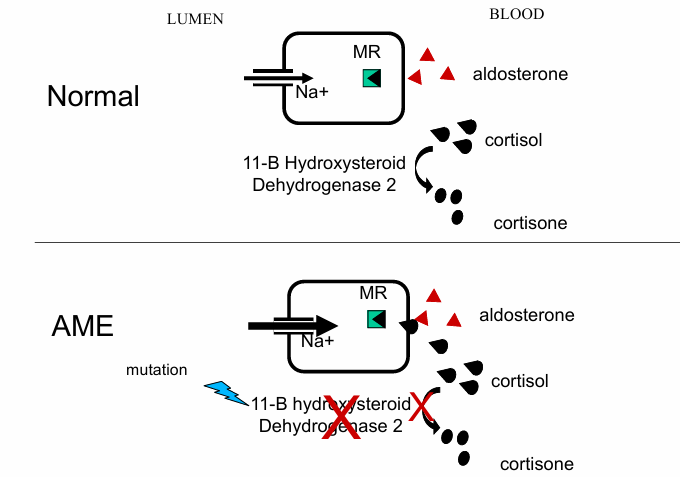

normal v. AME for lumen to blood

normal v. AME with licorice ingestion for lumen to blood